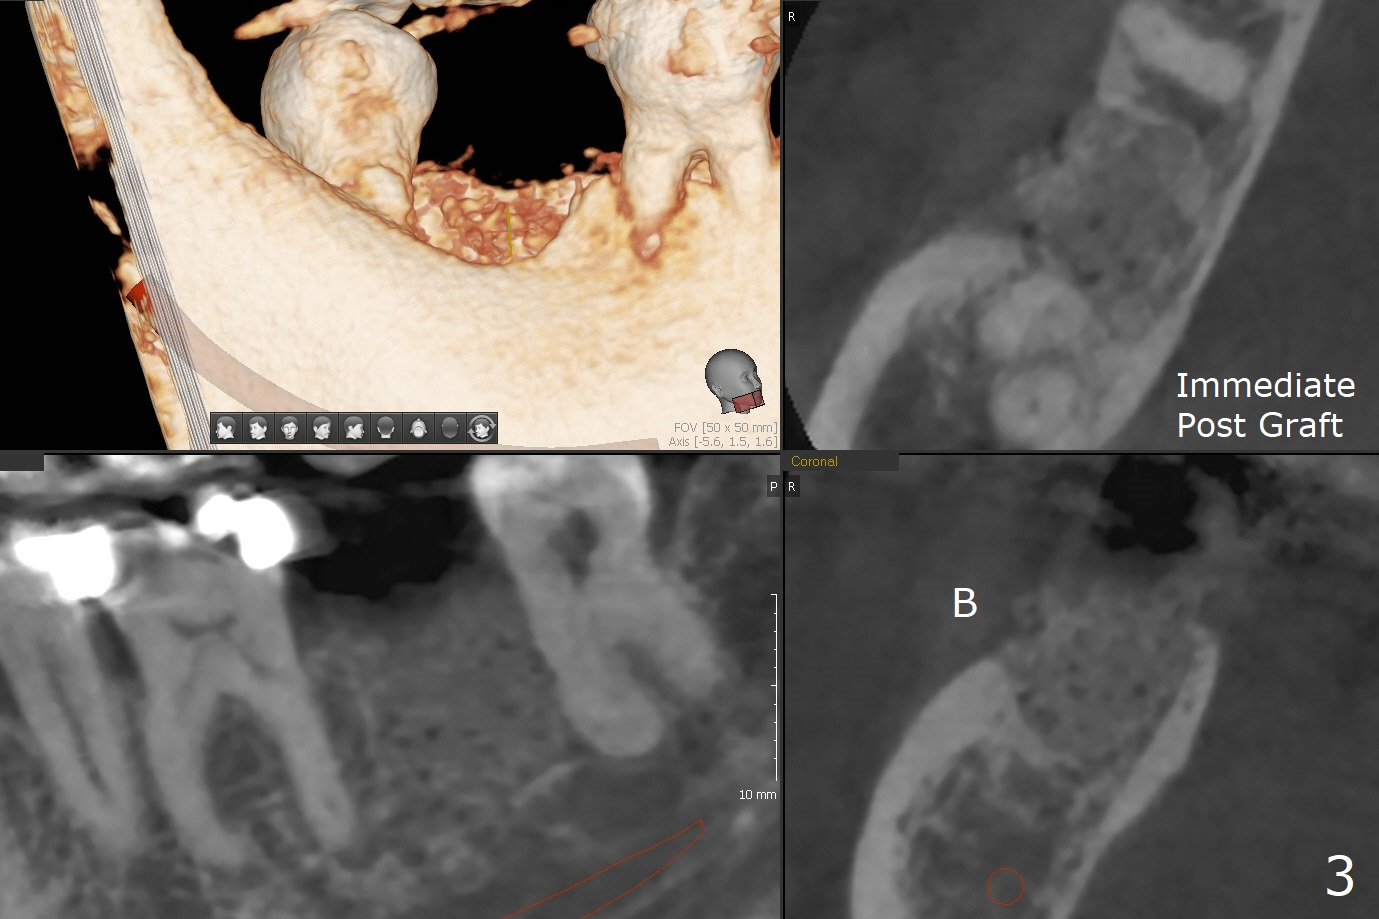

In fact the buccal gingival recession at #31 is asso-ciated with cervical caries perfor-ation (Fig.1 P). The debrided socket is packed with mine-ralized cortical: cance-llous mix (50:50) (better using mine-ralized cortical allograft (future particle size: 125μm – 850μm)) hydrated with ~ .25 ml of .3 mg/ml of rhPDGF-BB (one compo-nent of GEM21S, Fig.2,3). It is extremely difficult to close the socket opening with buccal defect with Osteogen Plug, 12x12 mm BioXclude and 4-0 PGA suture (Fig.4). Acrylic dressing is unstable in spite of several reline (Fig.5 A). Its replace-ment is GEM Cap RCM (regenerative collagen membrane), 9-12 month resorption time, which will be fixed in place with Perio Glue. Watch Video. In fact, 2 pieces of the reline dislodge in the 1st 2 days postop, while the whole piece 3rd days postop. The patient feels better when the acrylic dressing is out. It appears that the bone graft does not fall out, according to phone visit during coronavirus outbreak. A third method to close the buccal defect is to make mesial and distal release incisions (Fig.6) and transfer the flaps (Fig.7). In fact the bone graft gets lost, revealed over phone. Immediate implant is the most secure method to keep the bone graft. PRF may be more retentive. The fourth way is to place Cytoplast, which is fixed with spacer and periodontal dressing.